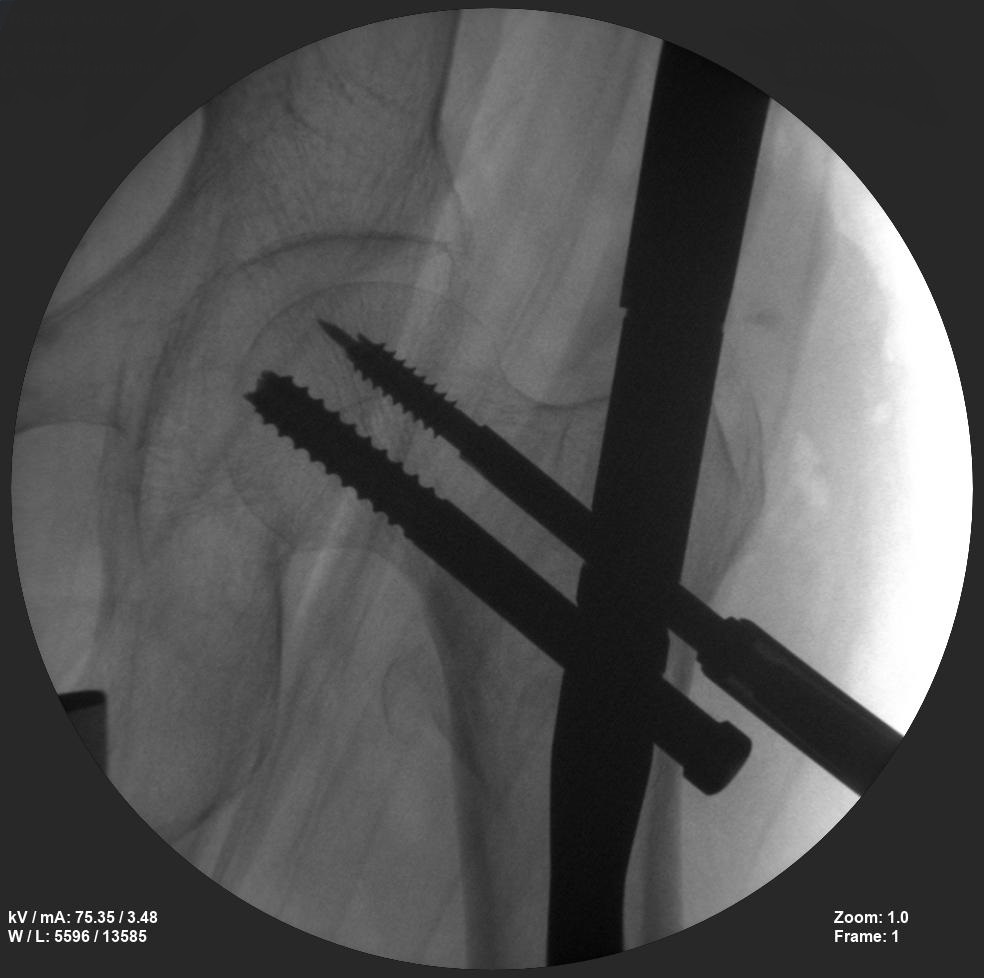

Skan-C plays a critical role in orthopaedic procedures, providing excellent imaging during interventional procedures, and allowing for precise localization and accurate treatment. The ability of Skan-C to offer dynamic visualization of visualization structures enhances patient safety, minimizes complications, and improves the overall effectiveness of orthopedic interventions.

CRIF - Closed reduction internal fixation

ORIF - Open reduction internal fixation

Clinical Evidence

Skan-C is a great C-arm for orthopaedic treatments for several reasons